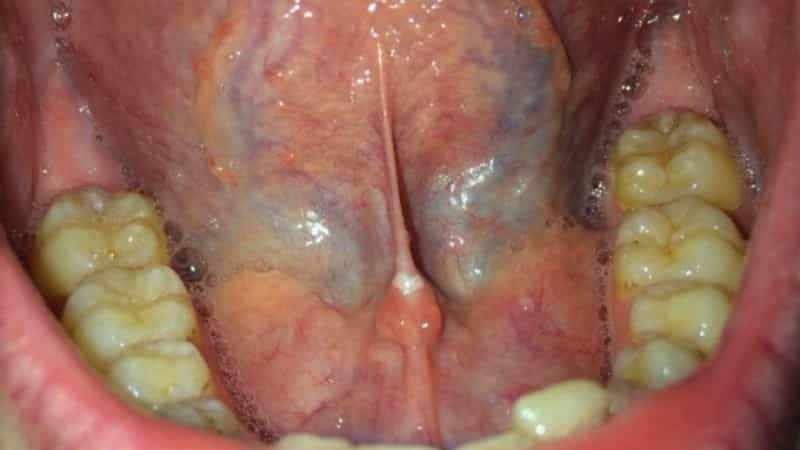

Когда появляются боли под языком, не всегда понятно, что именно является их причиной. Возможно, причиной болевых ощущений является воспаленная уздечка, которую можно легко увидеть, подняв язык. Уздечка представляет собой тонкую складку кожи, которая соединяет язык с ротовой полостью. Воспаление уздечки может вызывать проблемы при приеме пищи и разговоре, что может быть неудобным.

Болезненное состояние уздечки под языком требует выяснения причины и обращения к врачу. Возможными причинами являются травмы, инфекционные воспаления, заболевания зубов, аномалии структуры, аллергические реакции и различные виды травм. Кариес может вызвать быстрое распространение боли под языком, поэтому важно своевременно обратиться к стоматологу. Флегмона или абсцесс в полости рта может также вызвать сильные боли и воспаление уздечки. Инфекционное воспаление слюнной железы, аллергическая реакция и травмы также могут быть причинами боли и опухоли под языком. Воспаление уздечки сопровождается резкой болью при жевании, нарушением подвижности челюсти, речи и дыхания, а также повышением температуры и общим ослаблением организма. Мелкие травмы можно лечить самостоятельно, но серьезные повреждения могут привести к хроническим воспалениям. Травмы могут быть механическими, химическими или физическими. Механические травмы могут возникнуть при прикусывании языка, пломбировании, имплантации и восстановлении зубов, а также от ран от ножа или вилки. Химические вещества могут вызвать травмы и язвы на уздечке и других местах, а физические травмы могут быть вызваны попаданием кипятка, огня или пара на язык.

Часто болевые ощущения связаны с травмами мягких тканей или воспалением уздечки. Особое внимание следует уделить патологически короткой уздечке, которая испытывает большие нагрузки по сравнению с нормальной уздечкой.